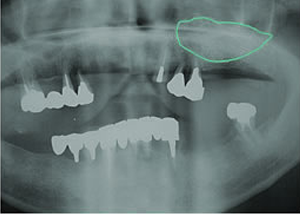

8.この部は薄い骨があっただけでインプラントの先端1/3を骨に埋入。あとはすべて骨を作ってあります。

上にのせた膜の中にチタンのフレームがわずかに映っています。

9.左下に3本 インプラント埋入

10.右下に3本 インプラント埋入